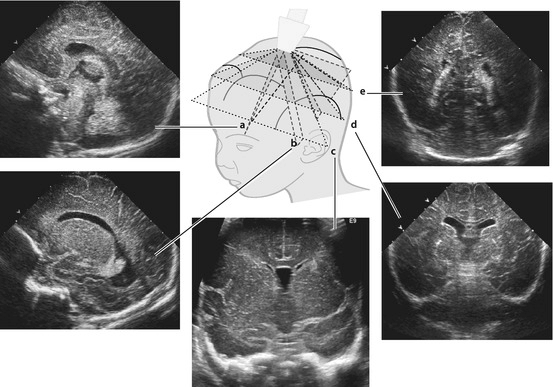

Научные изыскания на мозгах животных в конечном итоге привели к разработке универсального и безвредного способа регистрации суммарной электрической активности с поверхности черепа человека в режиме реального времени с помощью двух и более электродов. Сейчас этот метод известен как электроэнцефалография (ЭЭГ). Первая ЭЭГ была зарегистрирована с неповрежденного скальпа собаки в 1912 году «дедушкой ЭЭГ» — советским физиологом В.В. Правдич-Неминским (рис. 10А). А уже в 1929 году немецкий психиатр Ганс Бергер (которого называют «отцом ЭЭГ») опубликовал ЭЭГ-запись биоэлектрической активности с двух электродов, размещенных поверхности головы своего сына (рис. 10Б) [41].

С появлением ЭЭГ в начале ХХ века началась эпоха функциональной диагностики в неврологии: врачи получили возможность «слышать голоса» миллиардов нейронов живого головного мозга в режиме реального времени. Современные ЭЭГ-установки могут регистрировать сигнал от сотен электродов с усилением и миллисекундным разрешением (рис. 10В), что позволяет отследить минимальные изменения электрической активности нервных контуров в динамике. Для лучшего «перевода» ЭЭГ совмещают с регистрацией электрической активности сердца (электрокардиография), мышц (электромиография) и видеорегистрацией (чем пациент занимается в период мониторинга).

ЭЭГ сигнал очень достоверен, что играет важную роль в диагностике. Например, при обмороке или панической атаке ЭЭГ останется нормальной. И наоборот, эпилептиформная активность будет зарегистрирована, даже если у пациента нет внешних признаков эпилептического приступа (например, он просто лежит с закрытыми глазами). ЭЭГ-сигнал будет меняться при разном уровне сознания вплоть до глубокой комы, когда пациент никак не контактирует с внешним миром. ЭЭГ-сигнал исчезнет, если нейроны замолчали навсегда, поэтому ЭЭГ-протокол используется в установке факта смерти головного мозга. У некоторых неврологических заболеваний даже есть свой узнаваемый «ЭЭГ-почерк», а также существуют специфические ЭЭГ-сигналы для различных фаз сна, что используется в диагностике его нарушений для подбора эффективной терапии.

Разработка ЭЭГ-систем с множеством компактных электродов, а также математических алгоритмов обработки позволила вычленять из ЭЭГ-ритмов вызванные потенциалы — сверхслабые стереотипные ЭЭГ-изменения при воздействии раздражителей различной модальности или совершении действий. Рассчитываемый усредненный профиль вызванных потенциалов позволяет оценить работу зрительных, слуховых и двигательных нервных контуров по отдельности (рис. 10Д).